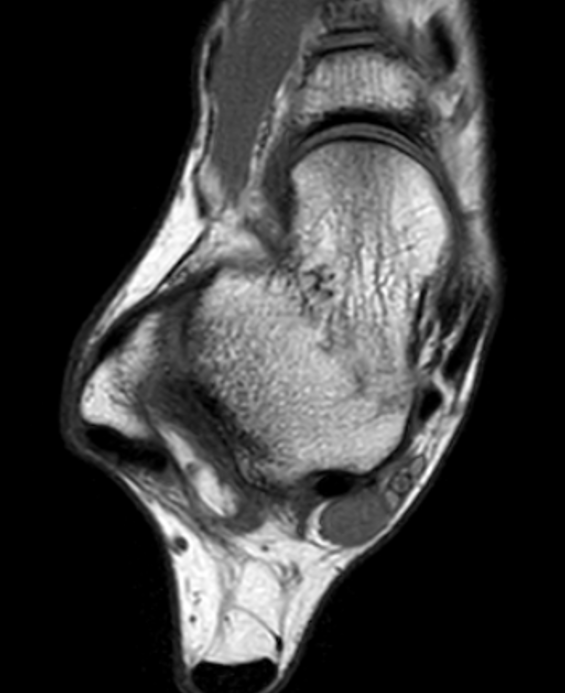

MRI - low signal on T1 and T2

PVNS anterolateral gutter ankle

PVNS with ankle joint / talus erosion